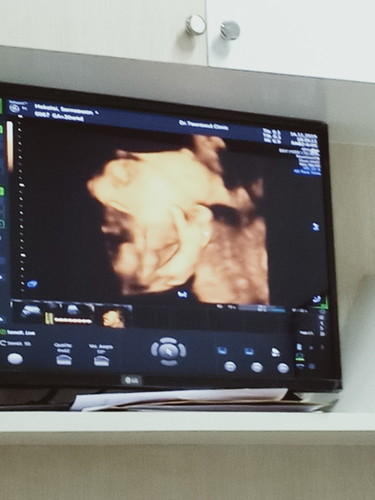

แม่ 31 w อัลตร้าซาวด์ น้องผู้หญิง น้ำหนัก 1437 กรัม #ทีมมกรา น้องน้ำหนักเท่าไรกันบ้างค่ะ กำหนด 19/01/63